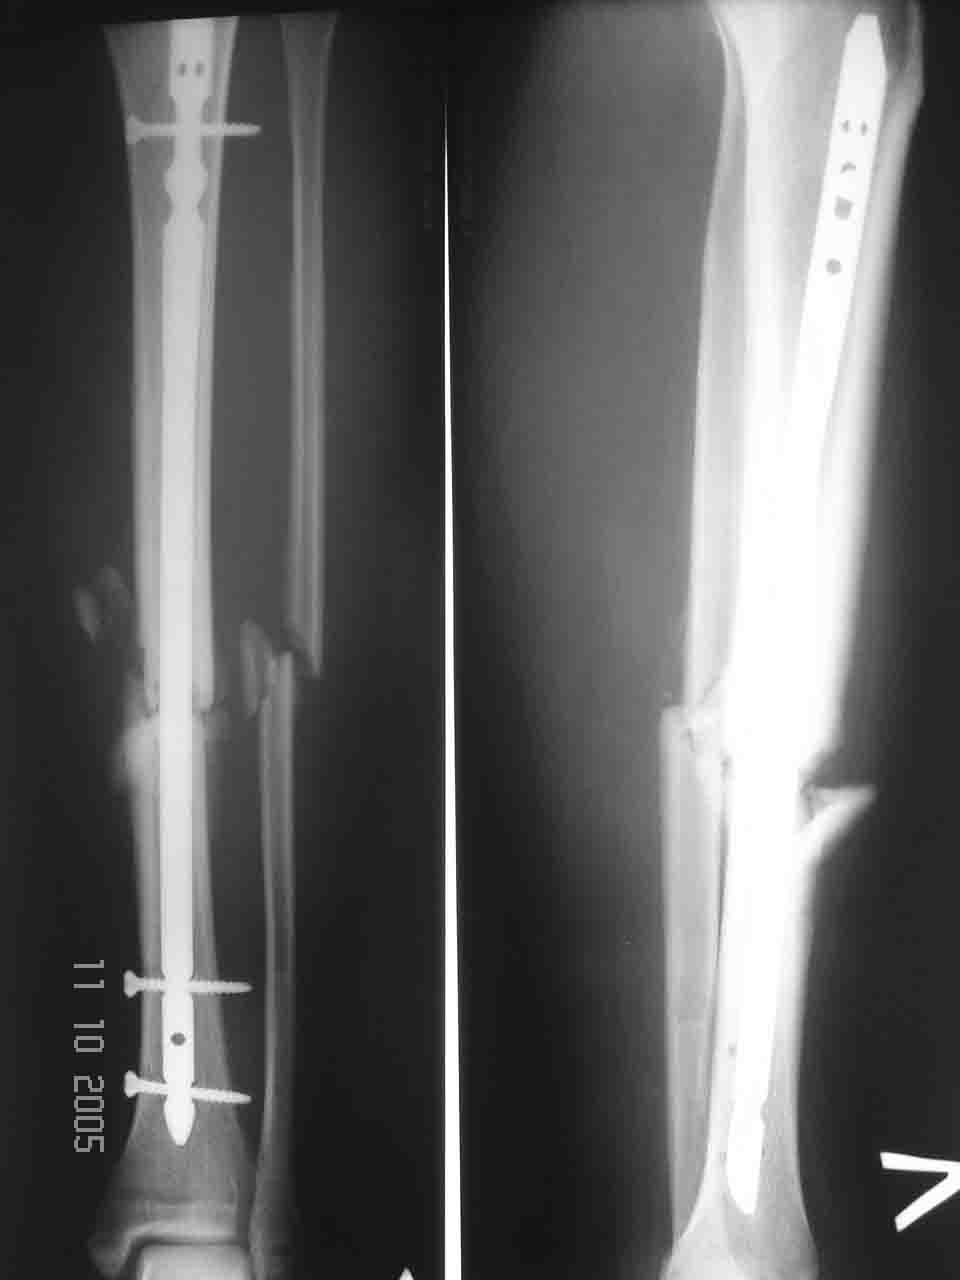

Если ни того, ни другого, наверно, стержень - оптимальный выбор. Сделал и забыл. Малоберцовую

рубить, похоже, не надо. Костную пластику я бы делать не стал.

Лучше взять гвоздь потолще, в центральный отломок винтов, кроме стандартных двух фронтальных, ввести еще. Внизу ввести в только в динамическое отверстие, если такие стержни у вас есть, или вообще не вводить. И нагрузку as tolerated сразу.

Да не так уж он короток, ~8-9 см. Все отверстия любого гвоздя будут выше зоны несращения. Конечно, винтов в центральный отломок лучше ввести побольше.

ДВ> Если уже гвоздь то тогда фирмы Synthes с рассверливанием.

Что с рассверливанием - это бесспорно, но почему именно Synthes? Можно любой другой, лишь бы диаметр побольше, от 10 мм. Так что пойдут и

Если в относительно коротком и широком центральном отломке будет лишь один динимический винт, возможна потеря фиксации. Наоборот, если в центральном отломке стержень фиксирован 2-3 статическими винтами, а

в дистальном винтов нет, либо динамический, будет только сближение по оси tibia, что и желательно.